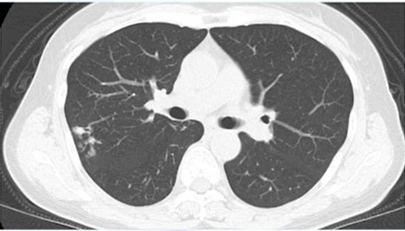

ちなみにCT画像はこんな感じです。

上葉舌区・中葉:主に肺の右中葉と左舌区に病変が集中することが多いです。

多発性の小結節影:両側の肺野に、小さな粒状の影が多数見られます。

気管支拡張像:肺の末梢にある気管支が拡張し、線路の線路やリングのような影として認められます。

本症例は、右中肺野外側、右下肺野に粒状影を認め、NTMを疑います。